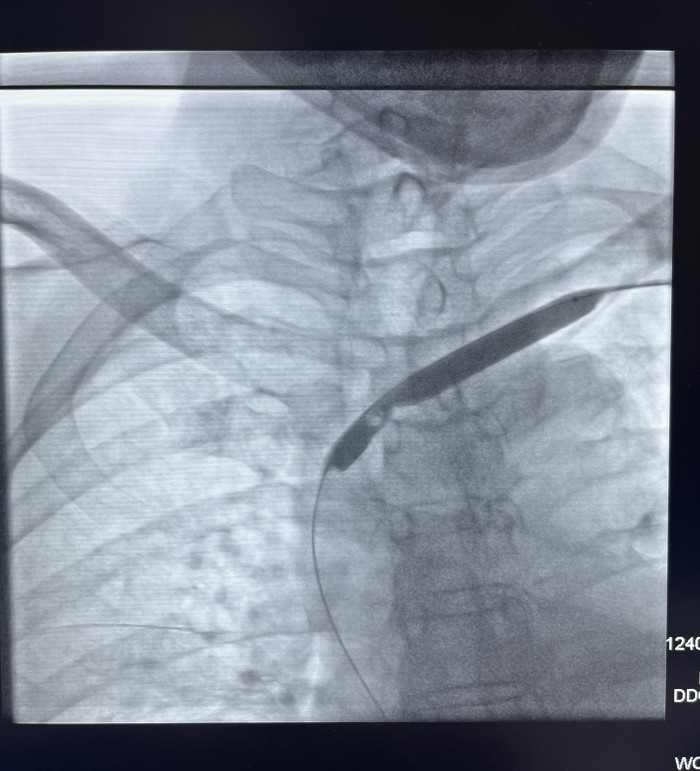

News近日,我院介入血管科成功开展一例左头臂静脉重度狭窄球囊成形手术,挽救了患者的左侧桡动脉-头静脉人工内瘘。

患者赵某,因两侧多囊肾致肾功能衰竭在我院行血液透析三年半。近一年来患者出现血透后左上肢肿胀并伴头面颈部表浅静脉怒张,近三月透析时人工内漏内血流量下降。经我院介入血管科副主任芮兵门诊详细询问病史及查体后收治该患者入院,行左上肢CTV及左上肢静脉造影检查显示:左头臂静脉起始部重度狭窄。在芮兵副主任医疗团队精心制定手术方案,排除手术禁忌后,成功实施了经皮左头臂静脉球囊扩张成形术,术后患者左上肢肿胀明显消退,透析时血流量>200 ml/min,可以完成透析。